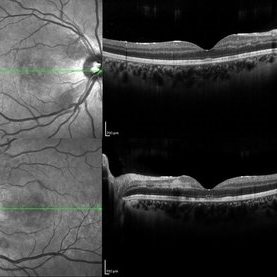

Plateau Fovea with Inner Retinal Thinning

Optical coherence tomography of the left eye of a 20-year-old male with Alport Syndrome. The patient did not present with any ocular or visual symptoms, yet the distinct "plateau contour" of his fovea was noted on OCT during his visit. The patient presented with 20/25 vision at the time of his visit. There was myelinated nerve fiber layer noted in both eyes, but these features had remained stable from his appointment three years prior. The physician noted that myelinated nerve fiber was a congenital change, and had not affected his vision or health of the eye, nor is a feature of Alport Syndrome.

Photographer: Olivia Rainey, OCT-C, COA

Imaging device: Heidelberg Spectralis

Condition/keywords: Alports disease, Heidelburg Spectralis, inner retinal thinning, left eye, optical coherence tomography (OCT), plateau fovea